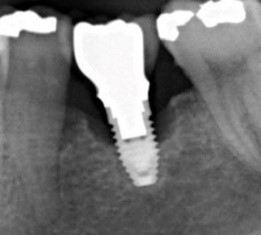

Au stade de « péri-implantite » il s’agit d’une atteinte inflammatoire des tissus mous entourant un implant. Le diagnostic clinique comprend un saignement au sondage, avec une suppuration quasi systématique, et une profondeur de poche péri-implantaire supérieure ou égale à 5 mm. Radiographiquement, un aspect radioclair de déminéralisation osseuse marginale supérieure ou égale à 2 mm entoure une partie plus ou moins étendue du corps de l’implant (fig 1 et 2).

Figure 1: suppuration au sondage d’une molaire atteinte de péri-implantite